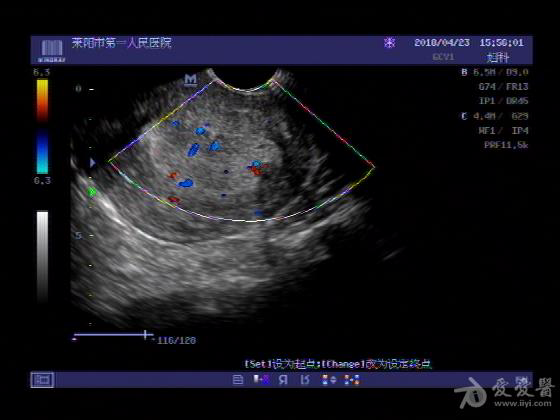

女,48岁,月经量多,两个月,一年前出现过类似现象,刮宫吃药后缓解。

超声可见:子宫内膜显著增厚,后肌壁内膜可见范围约3.27X0.90CM低回声区,CDFI显示较丰富线样血流,宫底宫腔内见类**状低回声结节。前肌壁见多发类圆形低回声结节。

超声提示:子宫内膜增厚(建议刮宫病理),子宫多发肌瘤

病理结果:内膜增生